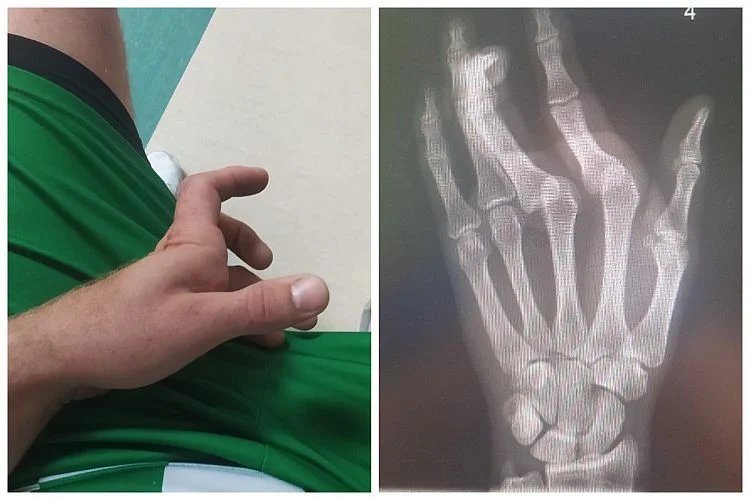

SportPiłkarze z Jabłonia bezbramkowo zremisowali z Twierdzą Kobylany. Już po 10 minutach z boiska musiał zejść grający trener naszych. Bartłomiej Jaszczuk po wyskoku w walce o piłkę spadł na dłoń. Bardzo szybko trafił do szpitala.

Skończyło się na strachu i dwóch zwichniętych palcach. Lekarze podjęli interwencję i Jaszczuk ma dłoń w szynie. - To był wyrównany mecz z solidnym rywalem. Graliśmy o zwycięstwo, jednak zabrakło nam przede wszystkim ostatniego podania przed bramką przeciwnika. Zostawiliśmy dużo zdrowia na boisku, ale niestety piłka nie chciała wpaść do siatki. Twierdza miała rzut karny w pierwszej połowie. Myślę, że wynik remisowy jest sprawiedliwy. Szanujemy punkt. W tym sezonie jeszcze nie przegraliśmy i chcemy, żeby tak pozostało jak najdłużej - mówi Kamil Jaszczuk, zawodnik Olimpii.